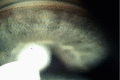

تنظير زاوية الغرفة الأمامية

تنظير زاوية الغرفة الأمامية. الهياكل الموصوفة: 1. خط شوالبي ، 2. شبكة صلبة (TM) ، 3. مهماز صلبوي ، 4. الجسم الهدبي ، 5. قزحية